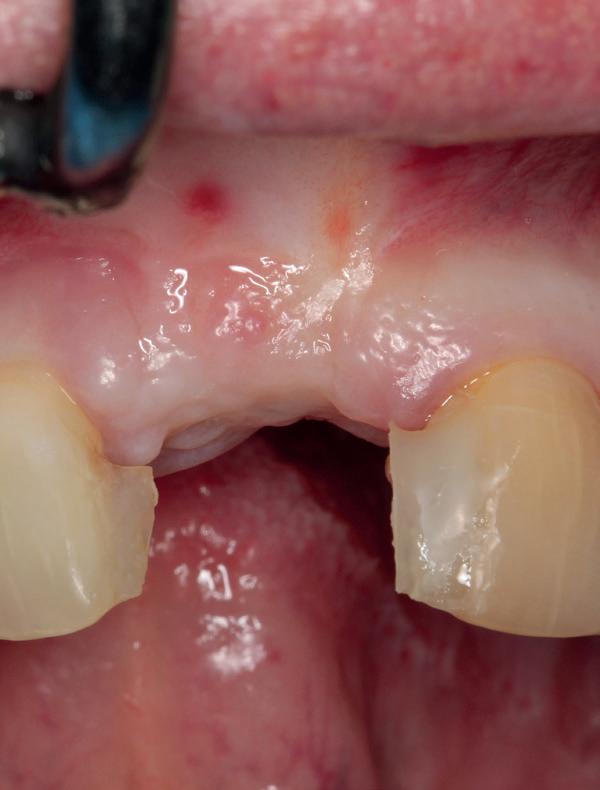

De patiënt, een 70-jarige man, had in het verleden tandheelkundige zorg ontvangen die zich kenmerkte door een ad hoc benadering. Er was geen sprake van een overkoepelend behandelplan of lange termijnvisie. De patiënt had naar eigen zeggen jarenlang niets

1. Studiofoto intake

aan zijn gebit gedaan behalve pappen en nathouden. Tandheelkundige zorg werd enkel verleend wanneer er zich een probleem voordeed (afbeelding 1, 3, 5).

Tijdelijke voorzieningen werden getroffen in de vorm van een etsbrug in de bovenkaak en een uitneembare voorziening voor de onderkaak.